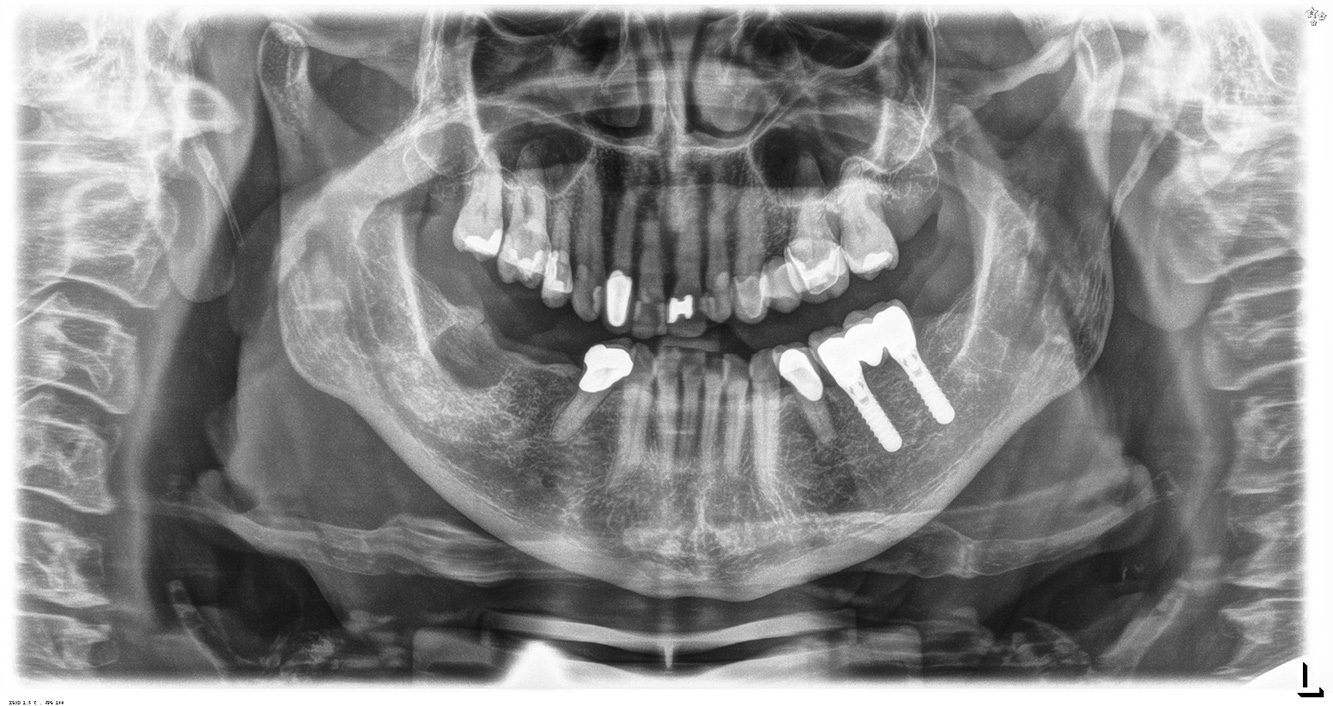

Der (mund)-gesunde Patient mit Implantaten

Der 55-jährige Patient gibt in der Anamnese an, keine Allgemeinerkrankungen zu haben und keine Medikamente einzunehmen. Die Lebensgewohnheiten des Patienten sind ebenfalls unauffällig. Der Patient hat einige zahnärztliche Restaurationen und zwei Implantate (2. und 4. Quadrant). Anhand der aktuellen Befunde lässt sich eine Gingivitis bei stabilem parodontalen Zustand am reduzierten Parodont (Stadium III, Grad A) feststellen. mehr Infos

Der gesunde Patient mit parodontaler Vorerkrankung & Periimplantitis

Ein 52-jähriger Patient stellt sich zur Präventionssitzung vor. Der Patient hat keine Allgemeinerkrankungen und nimmt keine Medikamente ein. Er hat verschiedene zahnärztliche Versorgungen und zudem zwei aktive kariöse Läsionen. Außerdem verfügt der Patient über vier Implantate (2., 3. und 4. Quadrant). Es zeigt sich eine parodontale Vorerkrankung (Stadium IV, Grad B). Derzeit herrschen stabile parodontale Verhältnisse, lediglich am Implantat regio 36 zeigen sich Sondierungstiefen (ST) von 5 mm. Zudem lässt sich eine Gingivitis feststellen. mehr Infos